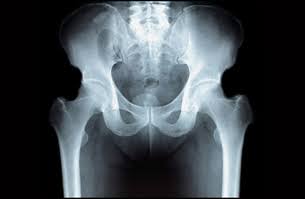

股関節は、

寛骨臼と大腿骨頭の組み合わせ

ですが、個性がとても大きく